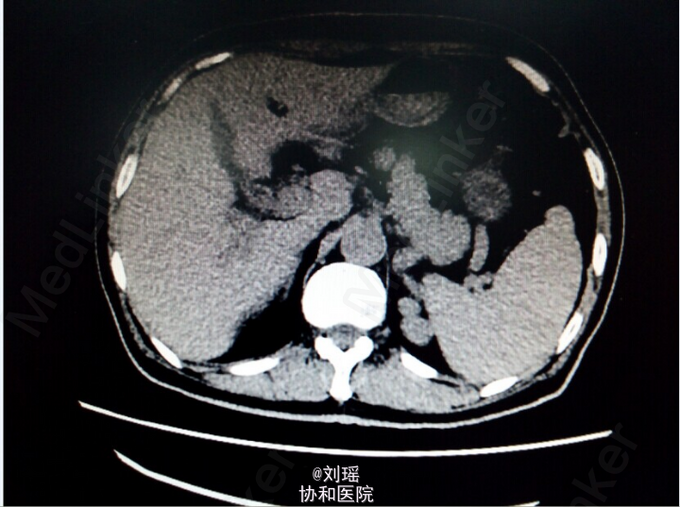

查体:生命体征平稳,慢性病容,皮肤巩膜重度黄染,右上腹T管,余无特殊。 辅助检查: 肝胆脾CT:右肾囊肿;胆总管粘液腺癌术后 T管造影:胆总管全段可见不同程度,不同大小之充盈缺损并不同程度狭窄,考虑为占位性病变。肝内胆管明显扩张。